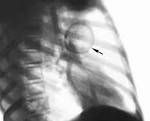

Q33.0 Врожденная киста легкого